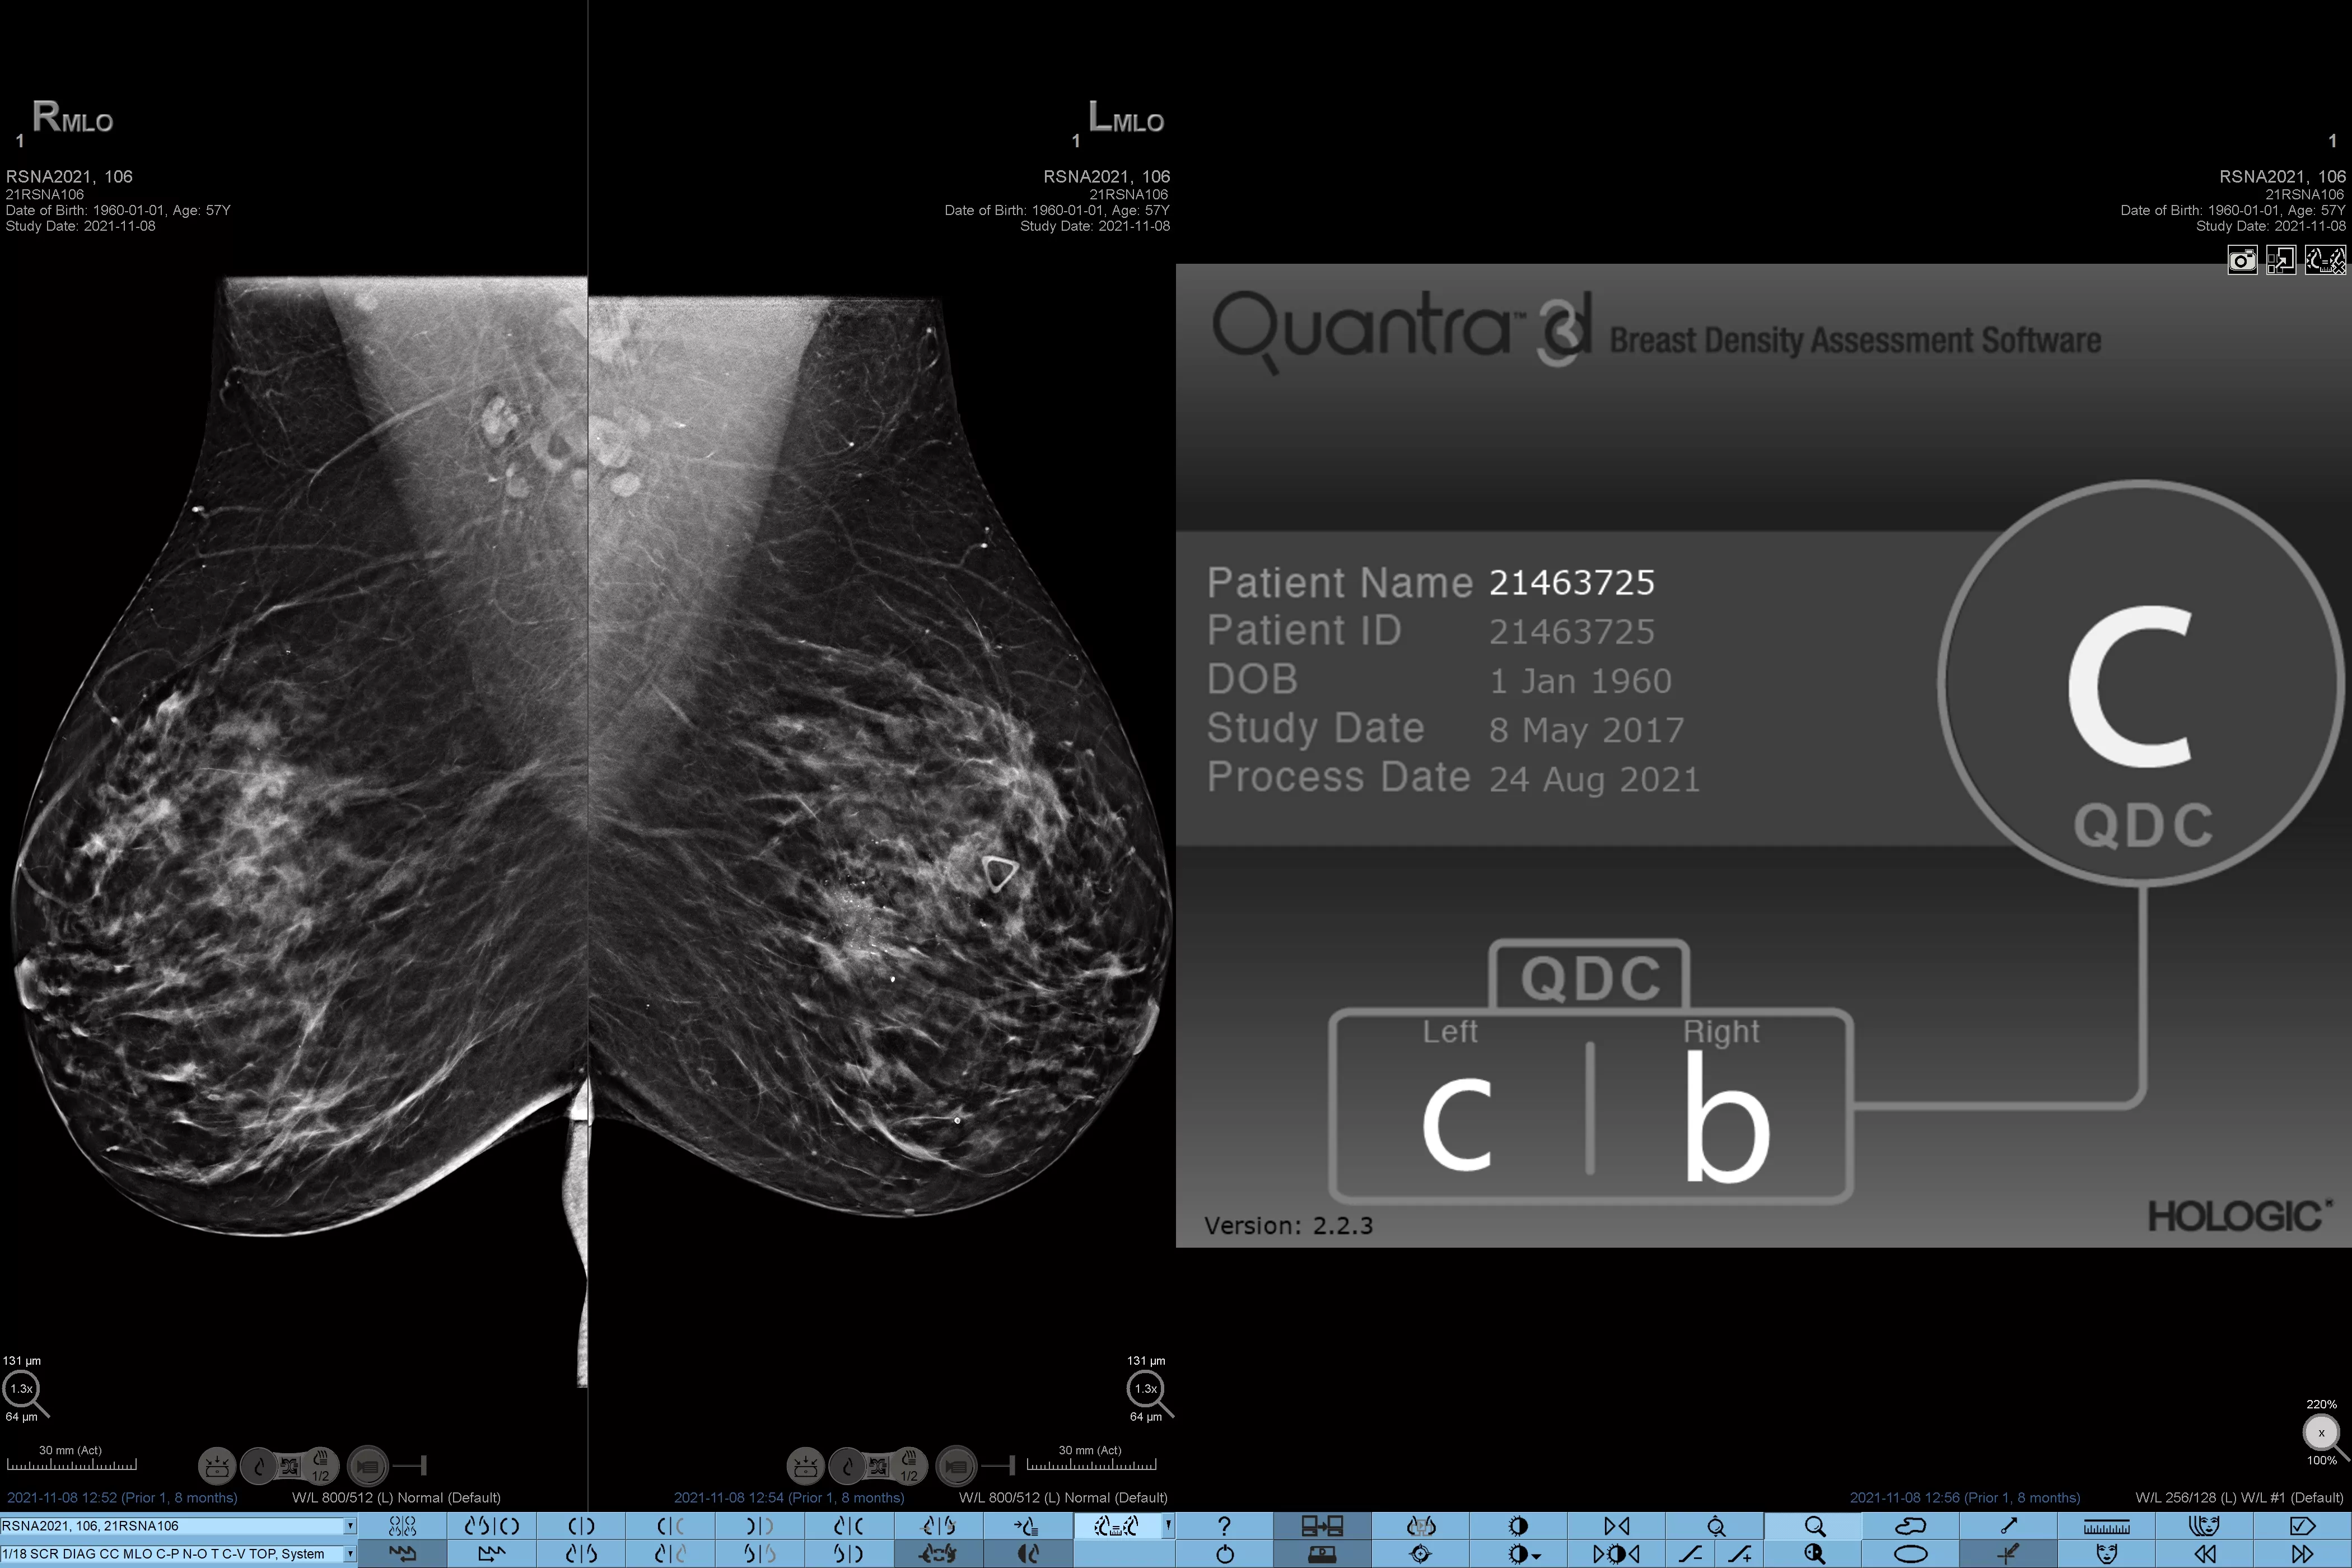

Det är känt att en hög brösttäthet ökar en kvinnas risk för bröstcancer.1 Behovet av noggrann och opartisk analys är därför kritiskt. Med hjälp av maskininlärning analyserar Quantra Technology-programvaran både 2D™- och tomosyntesbilder för fördelning och textur av parenkymal vävnad. Den kategoriserar bröst i fyra bröstkategorier utifrån sammansättning enligt riktlinje från American College of Radiology (ACR) BI-RADS Atlas 5th Edition.2

* Poängbedömningar baseras på ACR BI-RADS-kategorier enligt de reviderade riktlinjerna från American College of Radiation (ACR) BI-RADS Atlas 5th Edition. Detta motsvarar mönster och textur jämfört med volym vid bedömning av täthet.

8. Kategorier för bröstsammansättning enligt beskrivningen i ACR BI-RADS Atlas.